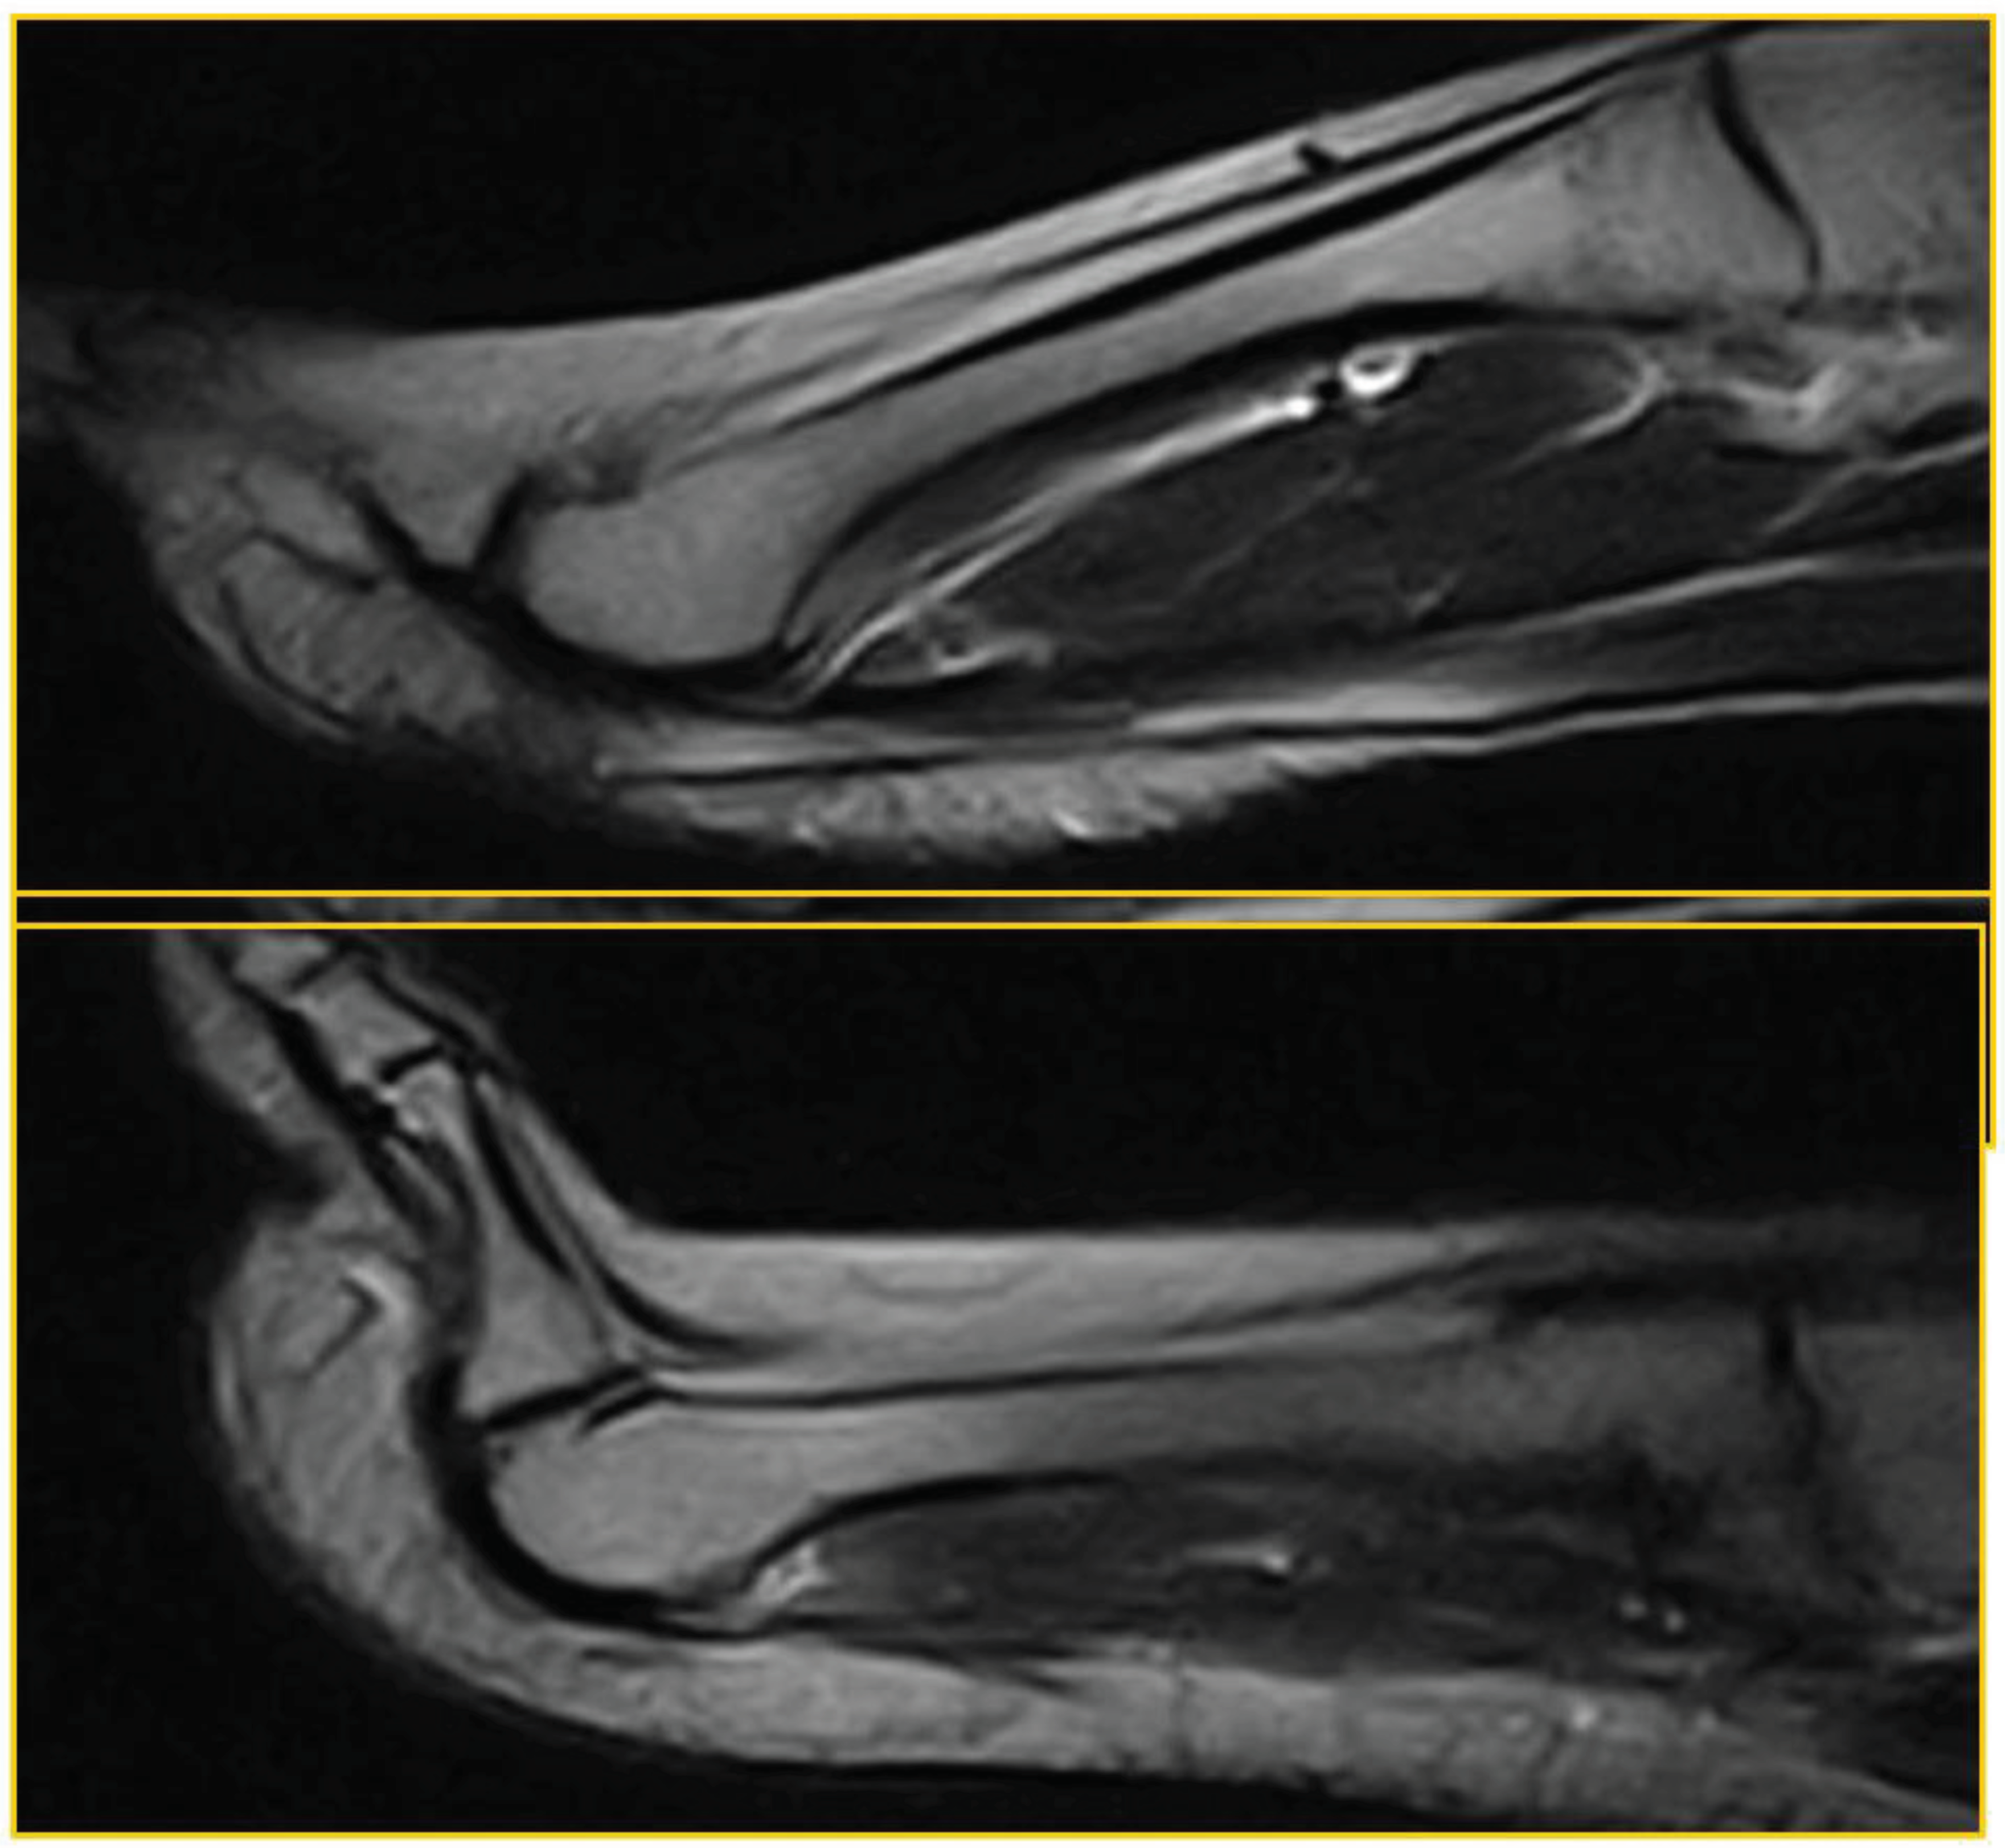

Patient 4: symptomatic (53 years, man). True positive: PP lesion visible both in standard position and during ST; dorsal subluxation is highlighted during ST (Figure 5).

The lesion affects the distal portion of the plantar plate, at the insertion at the base of the proximal phalanx; dorsal subluxation is observed in all slices during the stress test.

Figure 5. True positive.